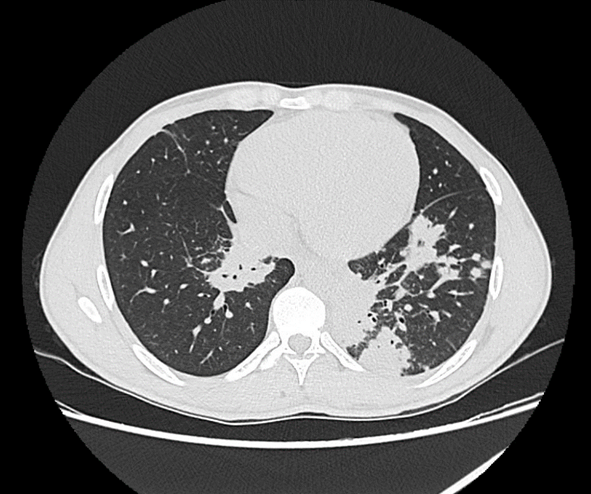

Actinomycosis is an infection characterized by the formation of abscesses, fistulas, and tissue fibrosis. It can mimic several other conditions, particularly malignancy and granulomatous disease. The suspicion is clinical, and the diagnosis is confirmed by identifying Actinomyces israelii or other Actinomyces spp. through microscopy and sputum culture or biopsy. Treatment involves prolonged antibiotic therapy. The case presented is of a young patient with persistent fever, cough, and no improvement with initial treatment. Computed tomography (CT) scan imaging showed slight consolidation in the lower lung base. Investigation for tuberculosis was negative, and positive for Actinomyces spp. Treatment was started with high-dose amoxicillin, with good progress and regression of symptoms, and a plan for prolonged treatment.